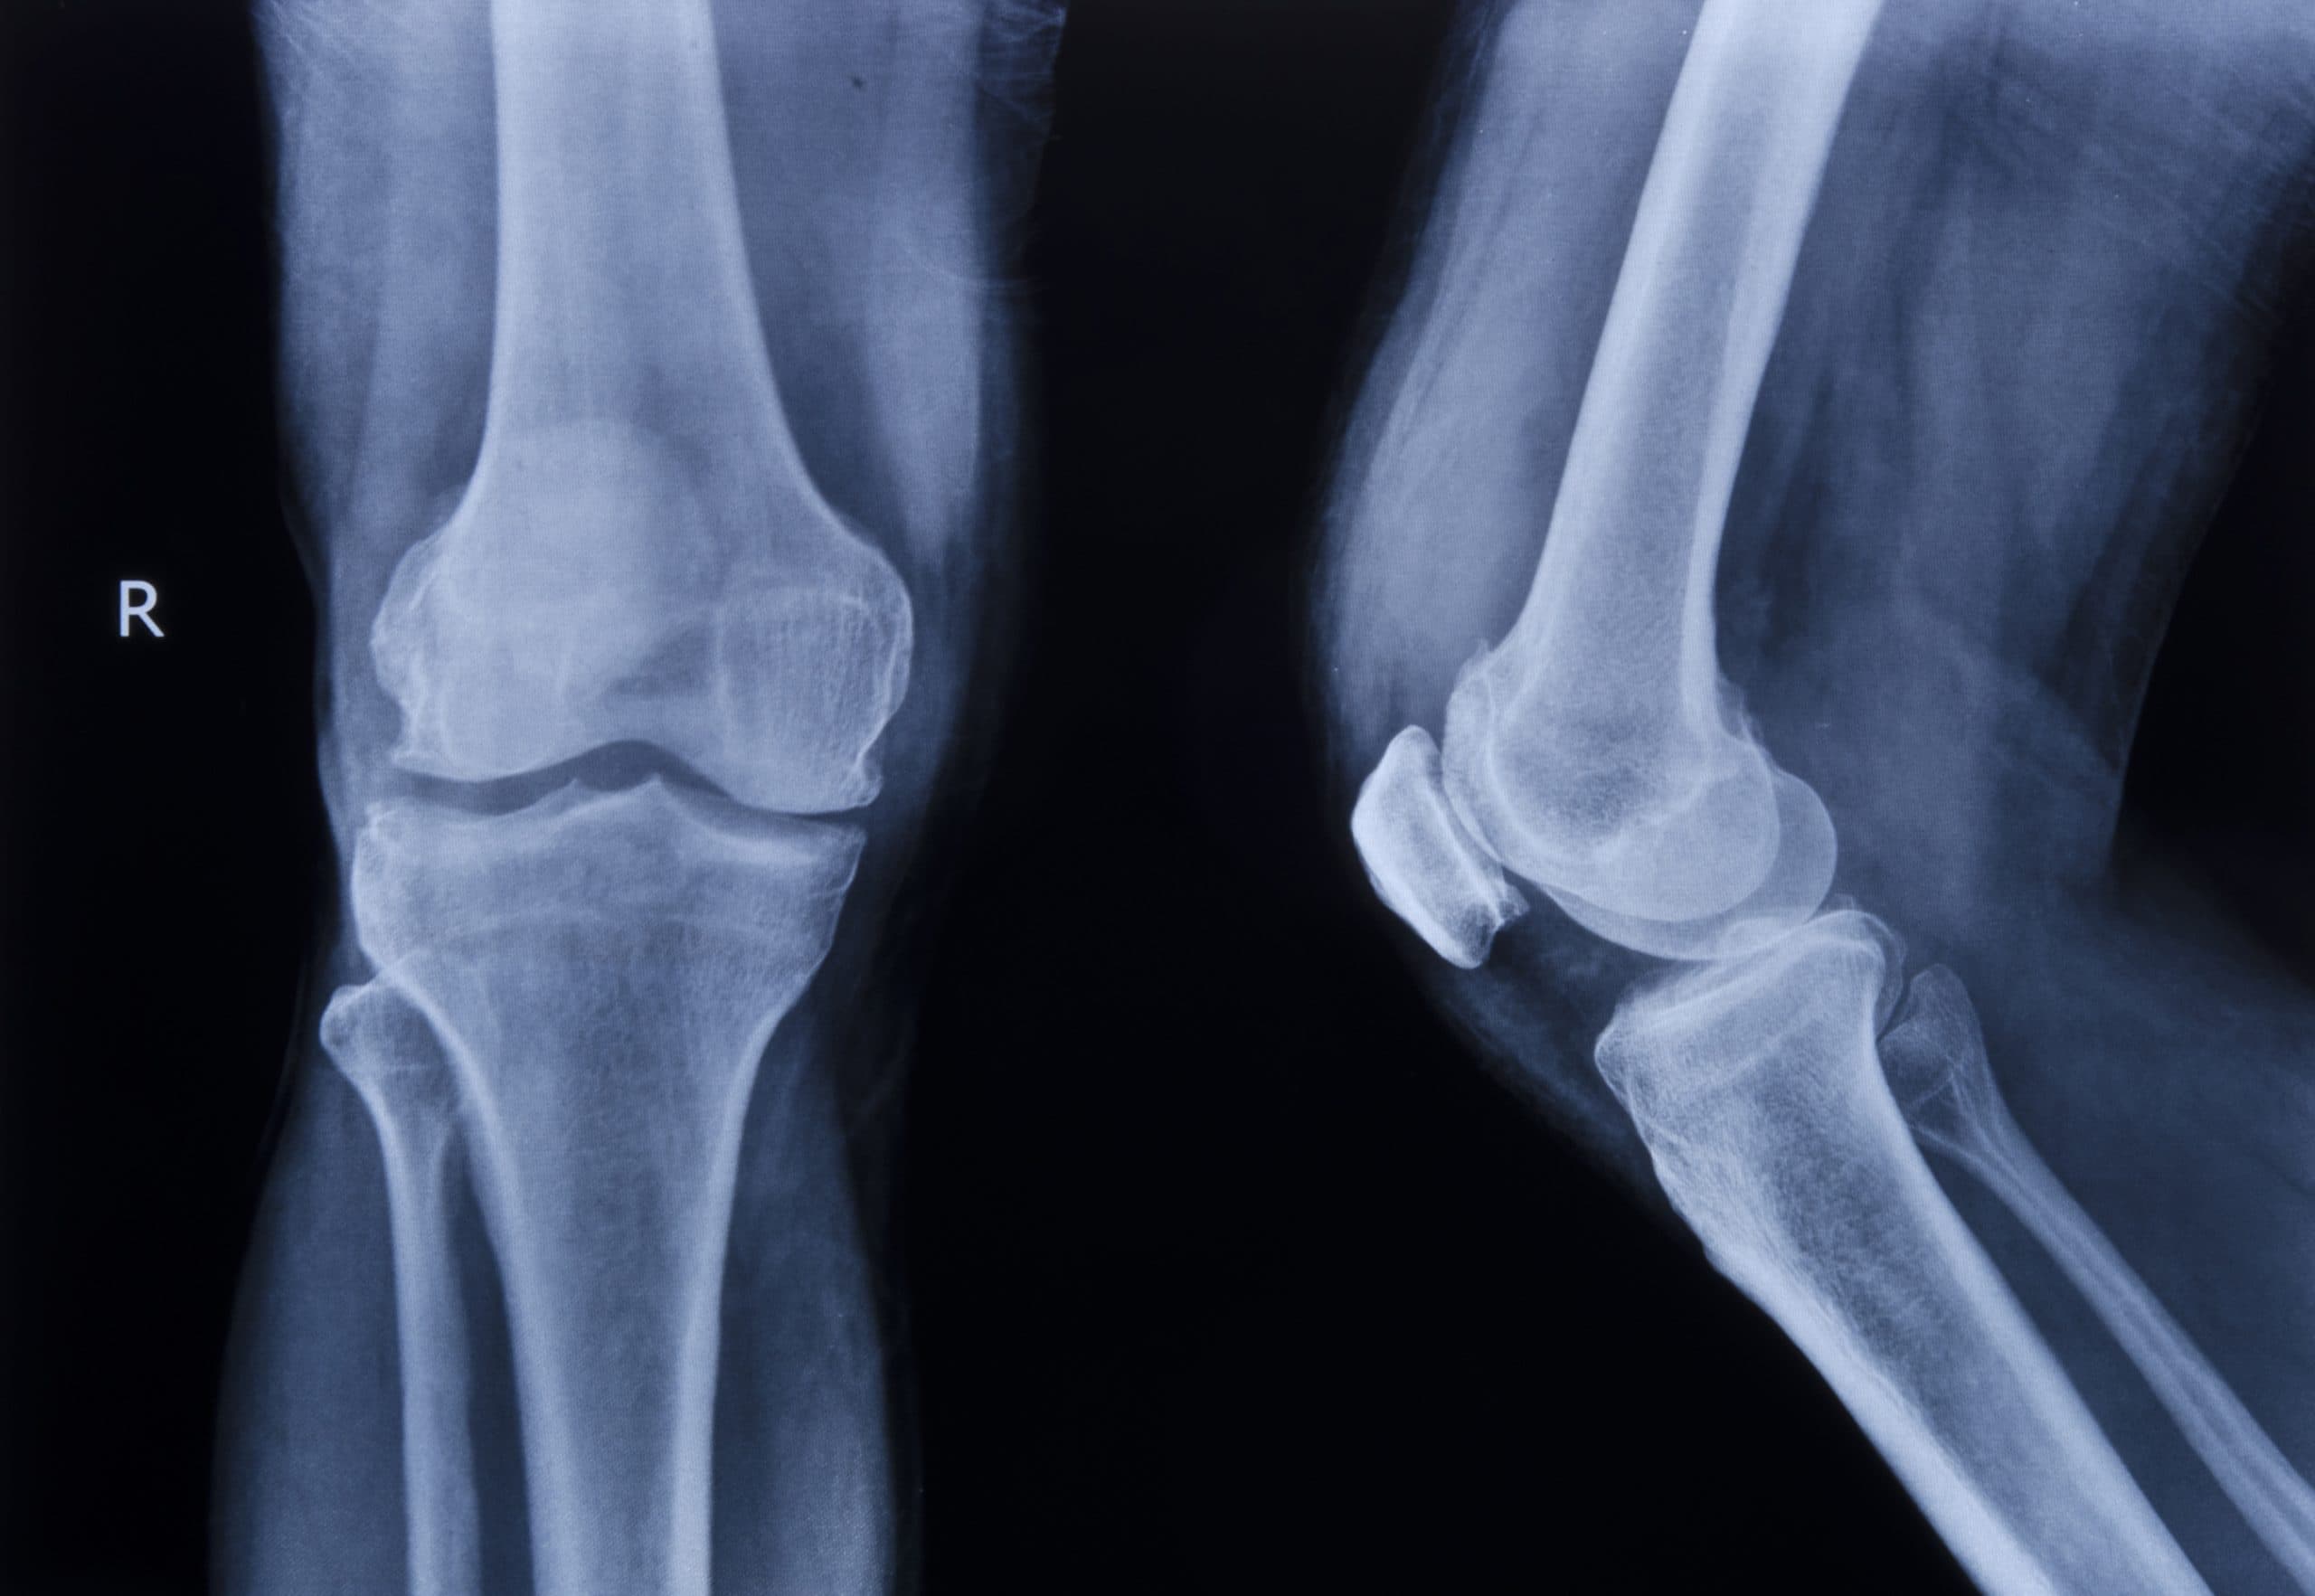

Comprehensive care for cartilage, meniscus and ACL injury, offering advanced injections, regenerative techniques and specialist surgical expertise.

Based in London’s prestigious Harley Street medical district, London Cartilage Clinic is a dedicated centre for the assessment and treatment of cartilage damage.

Our approach is informed by Musculoskeletal Regeneration Medicine, an interdisciplinary clinical framework combining orthopaedics, engineering, and regenerative science, and is tailored to both sports-related cartilage injuries and degenerative joint conditions.